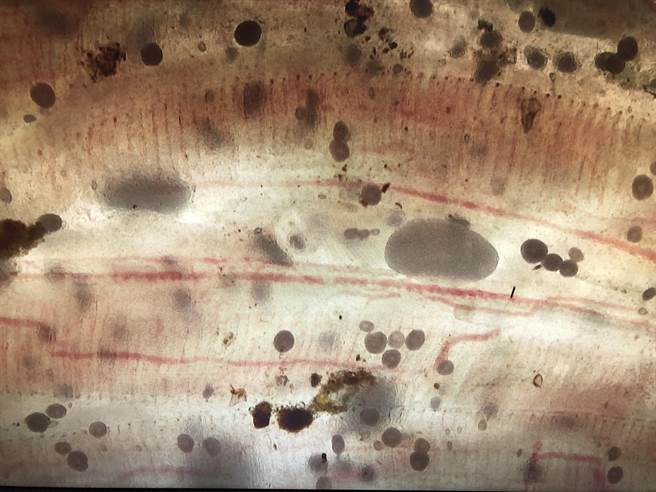

市府农业局长李建裕说,季节交替时期,往往水产动物寄生虫感染症好发期,每年因寄生虫疾病所造成的经济损失,不亚于病毒及细菌性感染症,尤其半淡咸水养殖鱼易感染卵圆鞭毛虫、海水白点虫、车轮虫及指环虫等。

李建裕指出,感染后的鱼只,其换气速度加快、食欲下降、磨擦身体、集体浮于水面、行动迟缓、移动麻痹、鳃盖逆立,鳃部的病变包括上皮细胞的膨大及增生、炎症反应、鳃丝的出血及坏死而导致死亡。